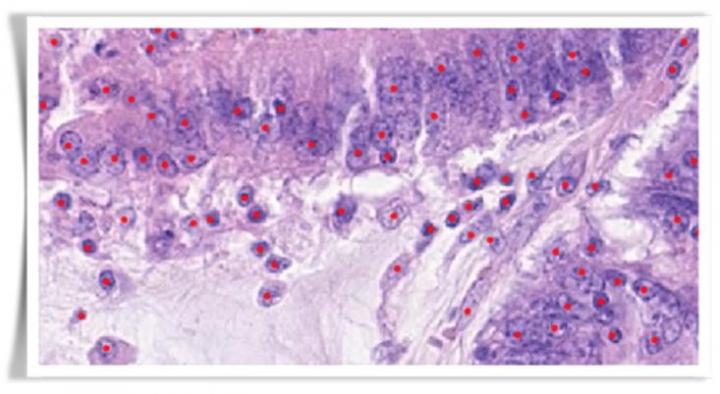

Gathering samples and data from the SKM Cancer Hospital & Research Centre, the project will involve digitally scanning slides of human tissue samples from oral cancer patients at the UHCW, and sophisticated computerised image analysis at Warwick, thereby generating a repository of important information about the different types of cancer cells which can be found in oral cancers in the subcontinent.

Professor Nasir Rajpoot at Warwick's Tissue Image Analytics (TIA) Lab will lead the project, using a revolutionary digital pathology system to analyse image data for cancerous samples from Pakistan's largest cancer hospital and research centre, leading to better diagnosis and treatment of oral cancers.

This information will be used to develop a computerised profiling algorithm, with which pathologists can potentially analyse cancerous tissue samples more accurately, and which can be used for targeted treatment options, and to better stratify oral cancer patients into various risk groups.